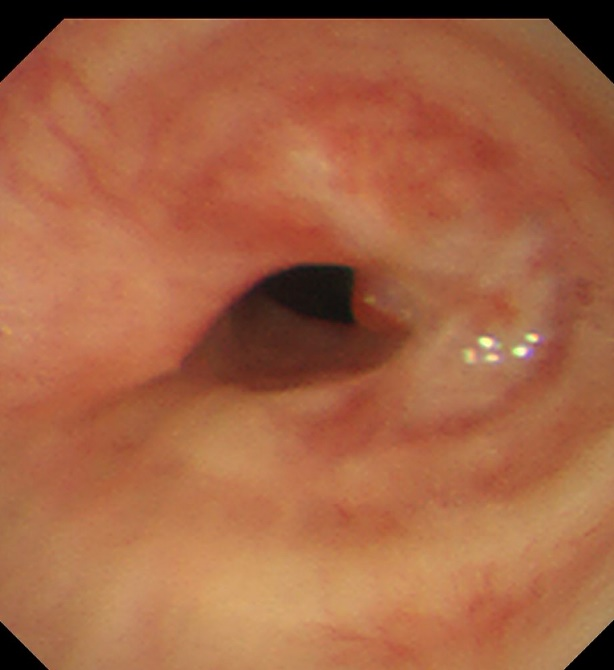

患者,女,50岁,因“外伤后呼吸困难2月”来到樱花动漫 全科医学科治疗。患者2月前因外伤致气管撕裂,在当地医院行气管修补术,术后出现进行性加重呼吸困难。患者来到我院住院后,稍微活动就会感到气促,已不能活动,肺功能显示重度阻塞性肺通气功能障碍,胸部CT显示气管下段重度狭窄,支气管镜检查显示气管下段距隆突2cm处重度瘢痕狭窄,最窄处仅4mm,随时都会发生窒息甚至猝死,手术迫在眉睫!

术后患者呼吸困难等症状得到了立竿见影的缓解,术后第二天复查支气管镜可见支架在位良好,管腔通畅。大大改善了患者的生活质量,患者于术后第三天下午顺利出院。